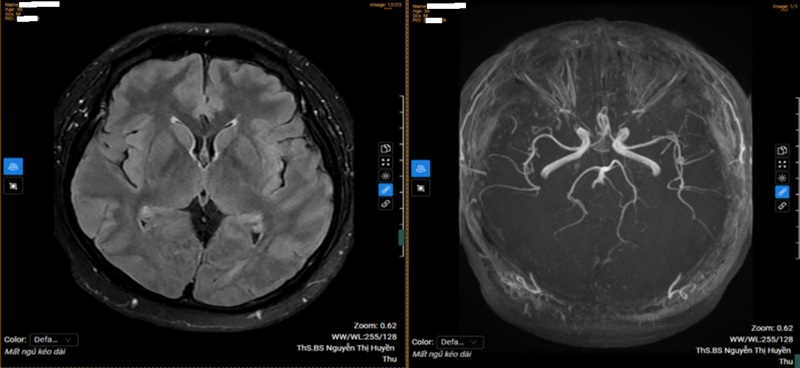

Thăm dò thần kinh chuyên sâu gồm cộng hưởng từ sọ não và điện não đồ không ghi nhận tổn thương thực thể. Tuy nhiên, đo lưu huyết não cho thấy giảm chỉ số lưu huyết ở hệ động mạch cảnh trong hai bên và hệ động mạch đốt sống - thân nền bên trái.

Kết quả chụp MRI sọ não của bệnh nhân